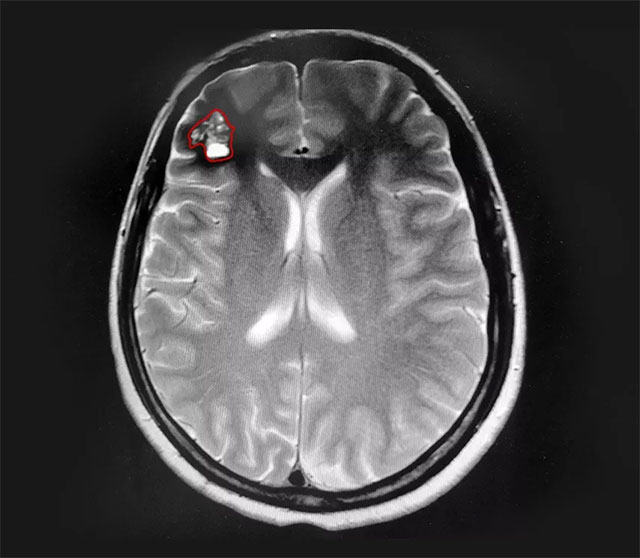

▲ 颅内海绵状血管瘤往往形似桑葚

上海蓝十字脑科医院神经外科主任沈建康教授指出,顾名思义,颅内海绵状血管瘤在影像学检查和手术过程中,看上去呈现为肿瘤样的团块,颜色为紫红色或褐色,表面往往像桑葚或爆米花,剖面呈海绵状或蜂窝状,质地有一定的弹性。

▲ 患者右侧额叶可见桑葚样团块

患者的头晕症状持续数年且于近期加重,已影响正常生活,结合病情进展和影像学资料,沈建康教授和神经外科6A病区侯增欣主任等专家开展了严谨的评估和讨论,认为患者具有手术指征。在告知手术风险并取得家属同意后,由沈建康教授主刀,为钱女士行血管瘤切除手术。

在电生理监测的保驾护航下,沈教授利用神经导航技术成功定位病变部位,并采用经脑沟入路技术,减少患者脑部皮质损伤直达病变部位。显微镜下可见,病变部位呈褐色桑葚状,周围脑组织黄染。“这是由于海绵状血管瘤自发性反复小量出血,造成的铁血黄素沉着。”沈教授解释道。借助先进的神经导航技术,在蔡司显微镜(双荧光)下,沈教授顺利切除血管瘤,并剔除黄染组织,术中无明显副损伤。